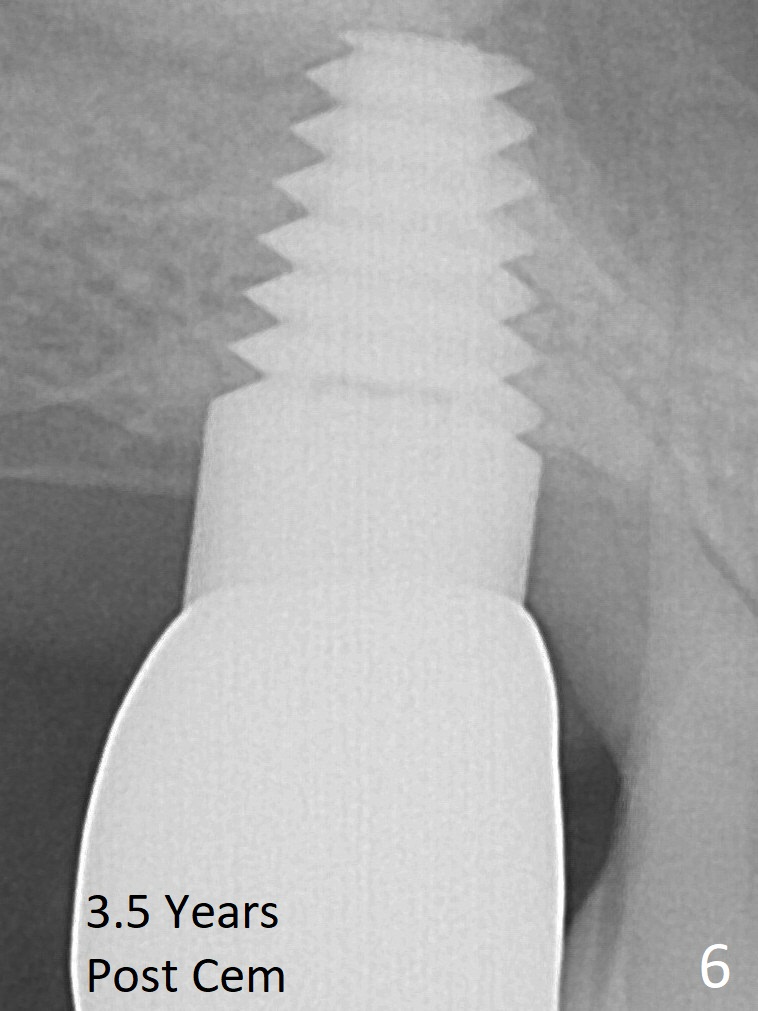

Mr. Kong is 43 years old. He has perio disease, for example #4 (Fig.1). The bone loss may be related to traumatic occlusion. The teeth #2, 14, and 15 are missing. Our primary goal is to restore these missing teeth as soon as possible. The bone height at the site of #2 is 5.8 mm. The Hounsfield units in the oral cortex, medullary and sinus floor are 400, 200 and 500, respectively. A trephine bur with outer diameter of 4 mm was used to start osteotomy (1,2). Probably due to limited access and dense bone, the trephine bur penetrated bone approximately 2 mm. A 2 mm pilot drill was used for further penetration, followed by 2.5-4.0 mm Bicon reamers for cylindrical osteotomy. A 4.5x11 mm tapered tap was used for bone expansion and sinus lift, followed by 5x11 mm tap (Fig.1). At higher magnification, it appears that the sinus floor had been lifted (Fig.1': *). A six by eleven mm tap was used. The apical end of the osteotomy felt to be intact and solid with a slender surgical curette. There was no sign of sinus membrane perforation, as confirmed by nasal blowing test. Harvested bone (from trephine bur and reamers) was pushed as apical as possible. A 6x11 mm implant was placed (Fig.2). It seems that taps/implant-related sinus lift increases the bone height to about 8 mm (Fig.2'). The thread portion of the implant is 6 mm. It appears that the 5x11 mm tap (Fig.1) and the 6x11 mm implant (Fig.2) invade the distobuccal apex of the first molar (*). Clinically there was some distance between them. Preop CT (axial section) may show the point (Fig.3: red circle stands for the implant; *: distobuccal apex of the first molar). The patient returns to office for follow up 1 week postop. The wound is healing normally around the stable implant. There is no percussion tenderness of the tooth #3. No bone resorption is observed 5.5 months postop (Fig.4), 7 months (Fig.5, Jan, 2015), 3.5 years (Fig.6) or 5 years 1 month (Fig.7) post cementation. At #14, bone height is 1-2 mm. Implant placement with sinus graft fails.